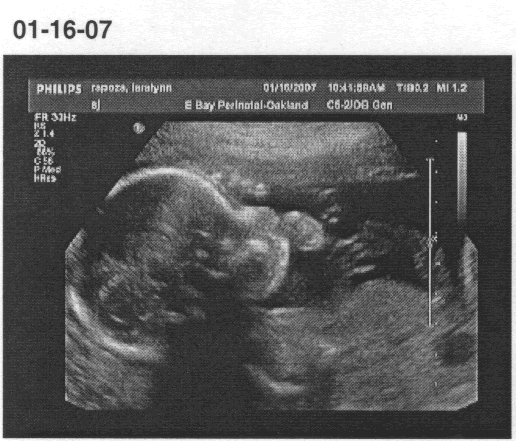

We had a follow-up ultrasound today (at 25 1/2 weeks). The doctor’s exact words were “Yup, 90% it’s a girl. But that’s definitely not a boy!” He even pointed out the labia between the legs, but said he refused to give 100% for girls, ever. I guess with the absence of parts you just don’t know for sure know until they’re born.

“Well, it’s about an 80% chance it’s a girl,” the doctor finally said, based on not seeing a penis but also on seeing two white lines in the crotch area. Apparently girls show three distinct white lines, and (from what I gather) boys have one light one. With its legs crossed, ours showed only two and they couldn’t rule out something else tucked between its legs. The doc was kind enough to arrange for a follow-up ultrasound in a month, but I’m not counting on knowing for sure until the little one pops out in four or five months. Oh – and everything else with the baby is great!